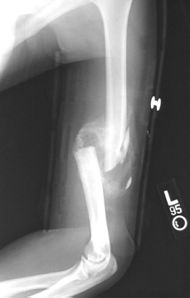

Communitive midshaft humeral fracture callus.jpg

Comminuted midshaft humerus fracture with callus formation.